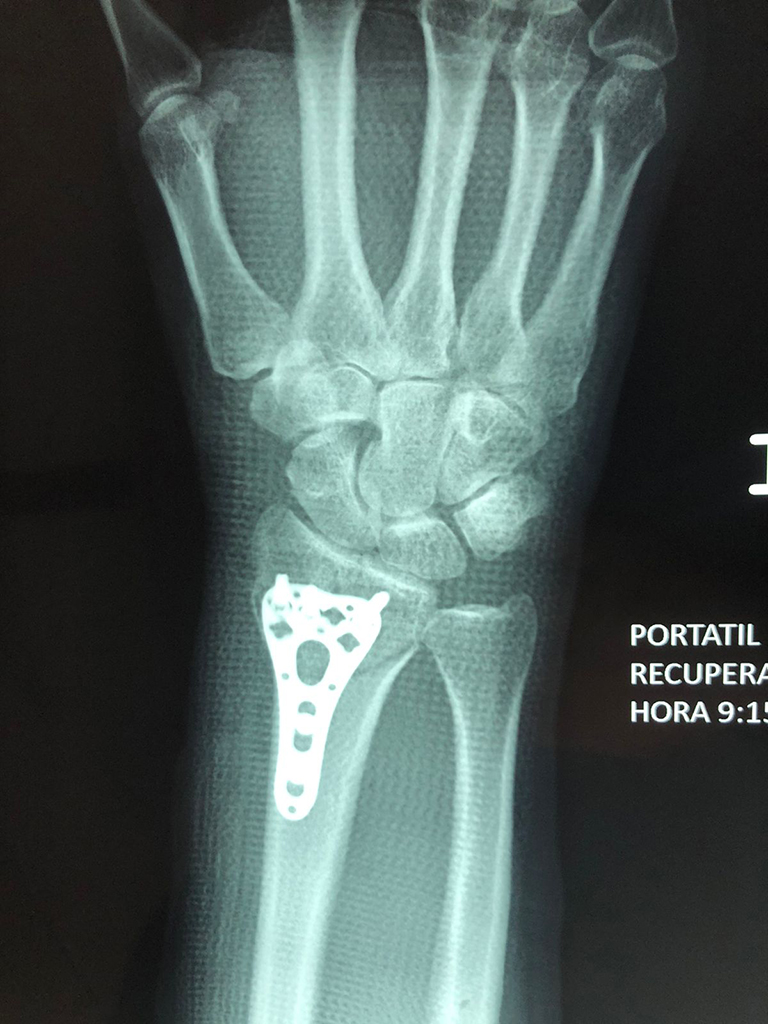

Cirugías de Húmero - Cirugías de Muñecas y Manos

Los procedimientos más comunes en cirugía de la mano son aquellos destinados a reparar traumatismos, incluyendo lesiones de tendones, nervios, vasos sanguíneos, y articulaciones; huesos fracturados; y quemaduras, cortes, y otros daños de la piel.